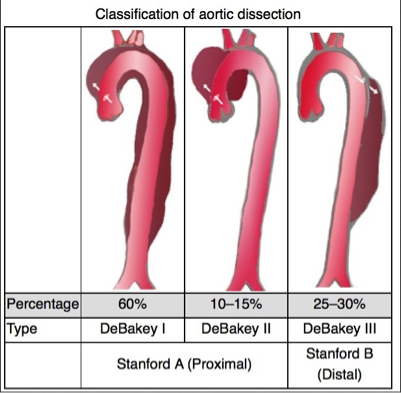

What does this refer to (in terms of aortic dissection)

Most simplified classification system EVER!

Stanford system divided into:

Stanford Type A (proximal)

_______________

Involves the Ascending aorta

What does this refer to (in terms of aortic dissection)

Most simplified classification system EVER!

Stanford system divided into:

Stanford Type B (distal)

__________

Does NOT involve the ascending aorta

What does this refer to

Stanford Typing System Aortic Dissection

Tx choice often depends on location

Stanford type A (ascending aortic) dissection

Immediate Open surgical mgmt superior to medical mgmt

Uncomplicated Stanford type B (distal aortic)

Medical mgmt preferred over surgical intervention

Repair if evidence of rupture or vessel occlusion

Medical management of aortic dissection